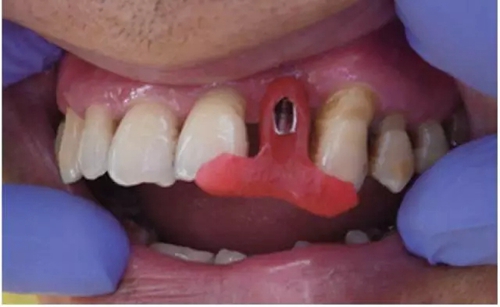

行影像學檢查(圖2);種植一枚Zuga 3.5*10 mm種植體,扭力≥35 N•cm,旋入愈合基臺(healing abutment)(圖3、4)。

圖3 22種植術(shù)前后照片